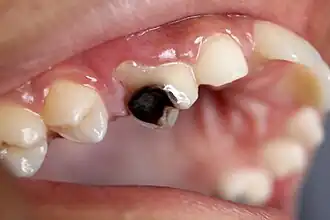

As the lesion continues to demineralize, it can turn brown but will eventually turn into a cavitation ("cavity"). A lesion that appears dark brown and shiny suggests dental caries were once present, but the demineralization process has stopped, leaving a stain. Active decay is lighter in color and appears dull.[14]

As the enamel and dentin are destroyed, the cavity becomes more noticeable. The affected areas of the tooth change color and become soft to the touch. Once the decay passes through the enamel, the dentinal tubules, which have passages to the nerve of the tooth, become exposed, resulting in pain that can be transient, temporarily worsening with exposure to heat, cold, or sweet foods and drinks.[15] A tooth weakened by extensive internal decay can sometimes suddenly fracture under normal chewing forces. When the decay has progressed enough to allow the bacteria to overwhelm the pulp tissue in the center of the tooth, a toothache can result, and the pain will become more constant. Death of the pulp tissue and infection are common consequences. The tooth will no longer be sensitive to hot or cold, but can be quite tender to pressure.

Depending on which hard tissues are affected, it is possible to describe caries as involving enamel, dentin, or cementum. Early in its development, caries may affect only enamel. Once the extent of decay reaches the deeper layer of dentin, the term "dentinal caries" is used. Since cementum is the hard tissue that covers the roots of teeth, it is not often affected by decay unless the roots of teeth are exposed to the mouth. Although the term "cementum caries" may be used to describe the decay on the roots of teeth, very rarely does caries affect the cementum alone.